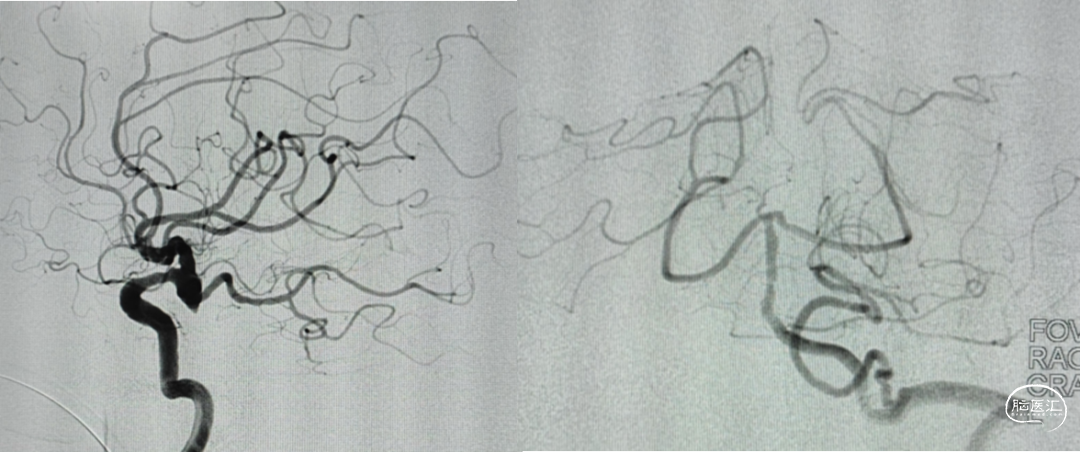

DSA:后交通动脉瘤

微导管塑形

echelon10(45)J-7(90右偏90)-15(90);echelon10(90)J-5(45右偏90)-15(90)

工作位